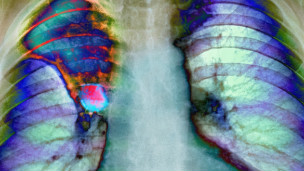

یوه څېړنه ښيي، چې په هرو درېیو کسانو کې یو کس په یوه ډول نه یو ډول پخپل ژوند کې د سرطان ناروغۍ نښې نښانې لري.

د سرطان ناروغۍ ته په کتلو سره، دغه ناروغي په بې وزلو او شتمنو دواړو هېوادونو کې ډېره شوې ده، چې په دغې ناروغۍ اخته کسانو لکه د اعدامېدونکو کسانو په سترګه کتل کېږي.